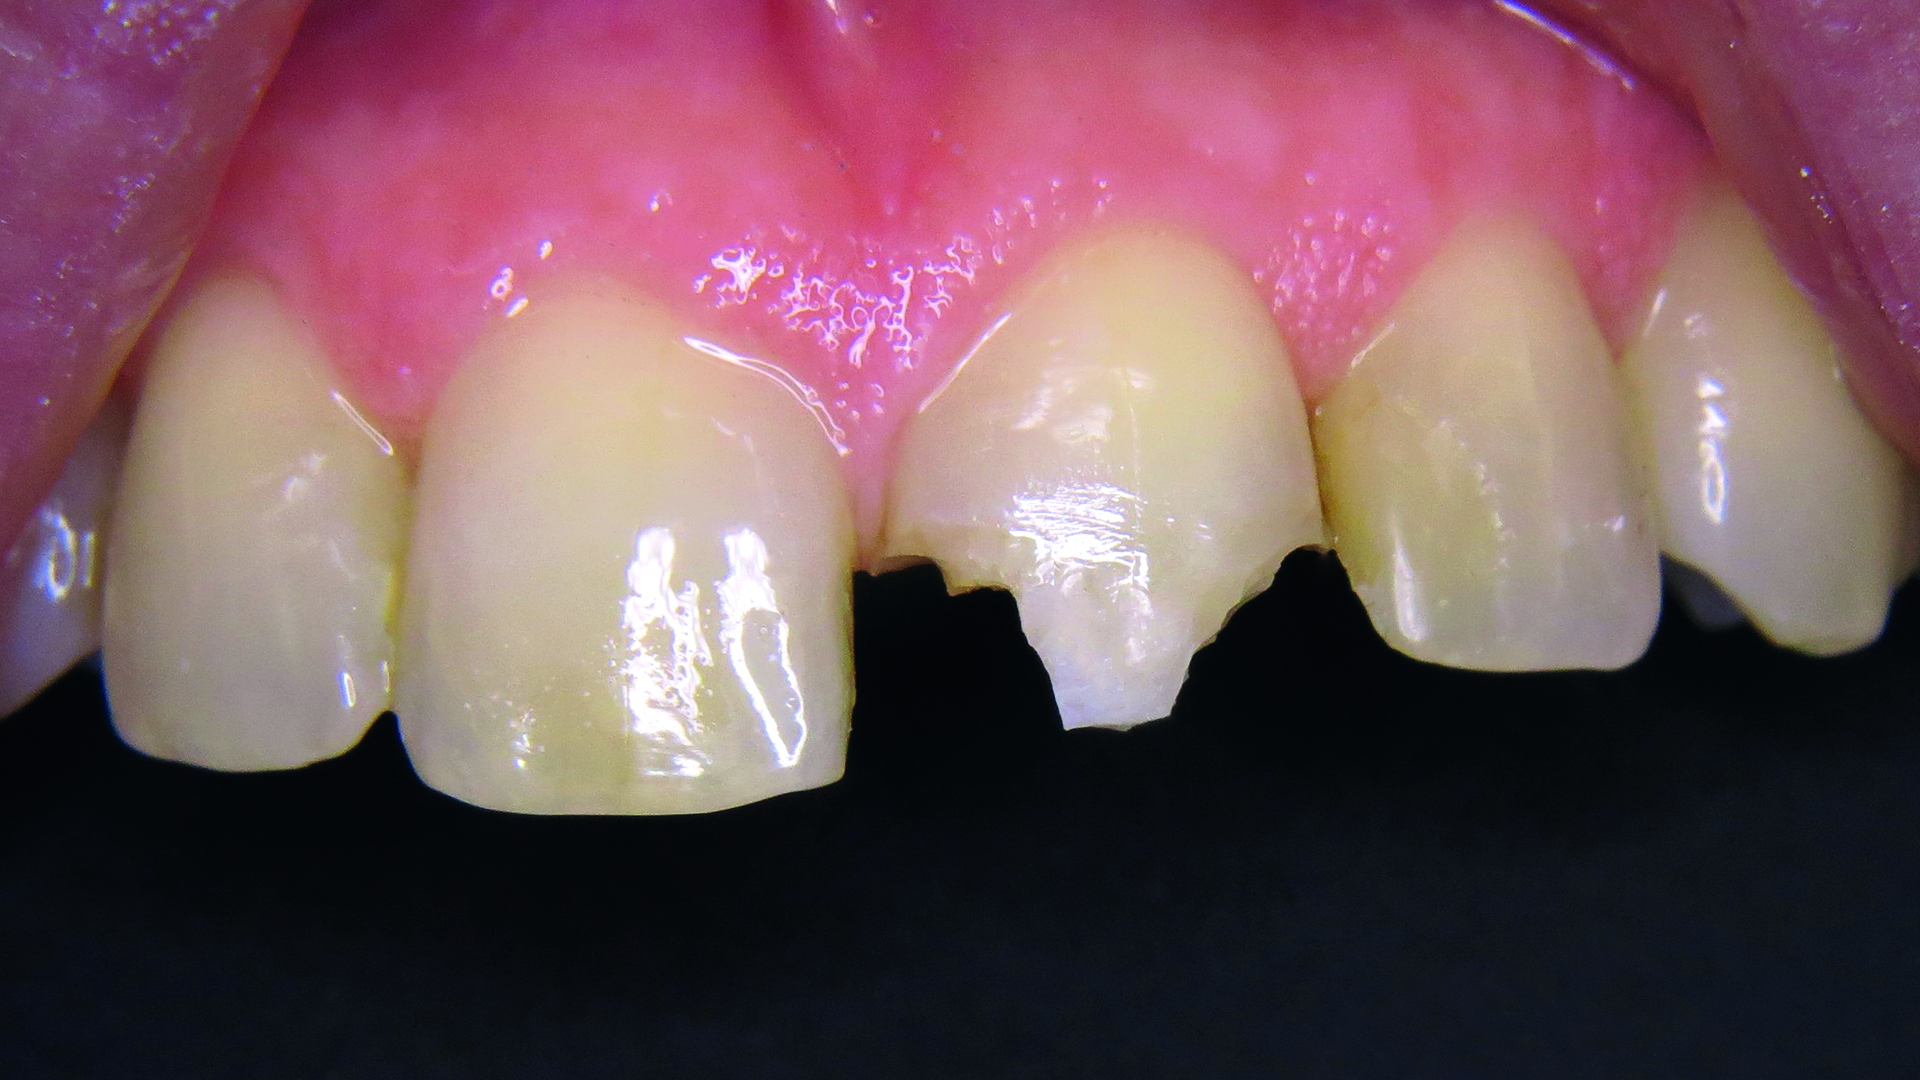

Podano miejscowe znieczulenie nasiękowe preparatem Ultracain D bez adrenaliny (Sanovi-Aventis GmbH, Niemcy), po czym oczyszczono zęby przednie pastą Cleanic bez fluoru (KERR GmbH, Niemcy). Wadliwe wypełnienie usunięto wiertłem z nasypem diamentowym i różyczką, kontrolując dostęp wilgoci (ryc. 4).

Ryc. 4. Stan po usunięciu odbudowy.